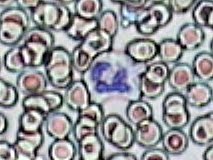

Imágenes tomadas de las preparaciones de los alumnos de 3º ESO sobre un frotis sanguíneo